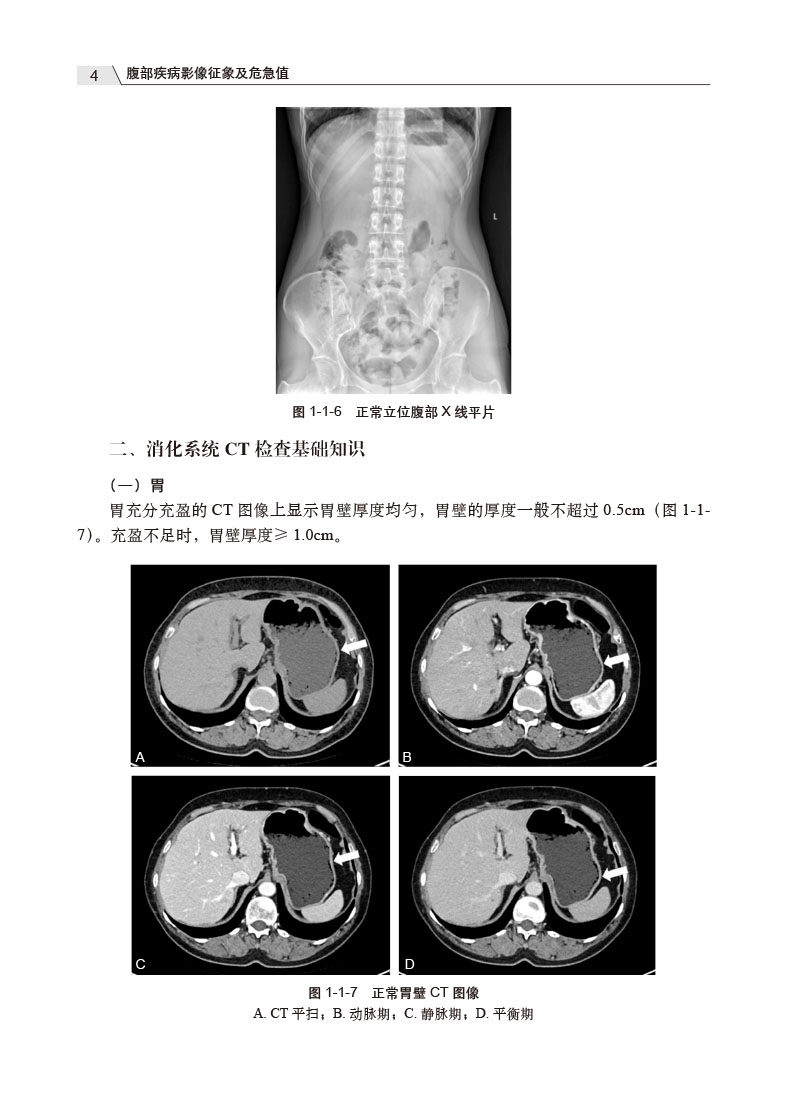

二、消化系统CT检查基础知识 4